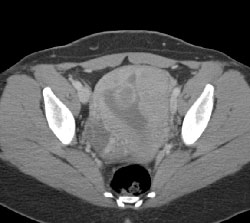

Fetus on the Run